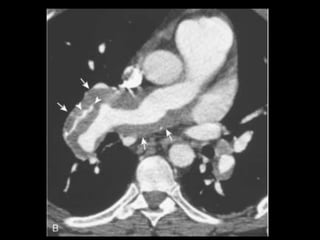

Embolia Pulmonar Patologiacomum e representa a terceira causa de morte nos EUA; Resulta de um trombo formado nos sistema venoso; Radiografia de tórax tem valor limitado: tem mais valor em excluir outras condições; Exame de escolha: angio-TC(MD); Acurácia da TCMD depende: do tamanho da artéria afetada e do tamanho do êmbolo;

Embolia Pulmonar Diagnóstico deembolia aguda na TC com contraste é baseado na visualização direta de falhas de enchimento parciais ou completas dentro das artérias pulmonares; Sinal da “rosca”; Sinal do “trilho de trem”; Outro sinal útil: formação de ângulos agudos com a parede vascular, a perda completa da opacificação e o aumento do diâmetro do vaso acometido.

Embolia Pulmonar Tromboscrônicos: com frequência aparecem como defeitos de enchimento em forma de crescente ou laminares aderidos às paredes da artéria pulmonar; Calcificações podem estar presentes; Armadilhas: tempo de delay, volume de contraste, sangue não opacificado oriundo da veia cava inferior e do átrio direito( interrupção transitória de contraste);